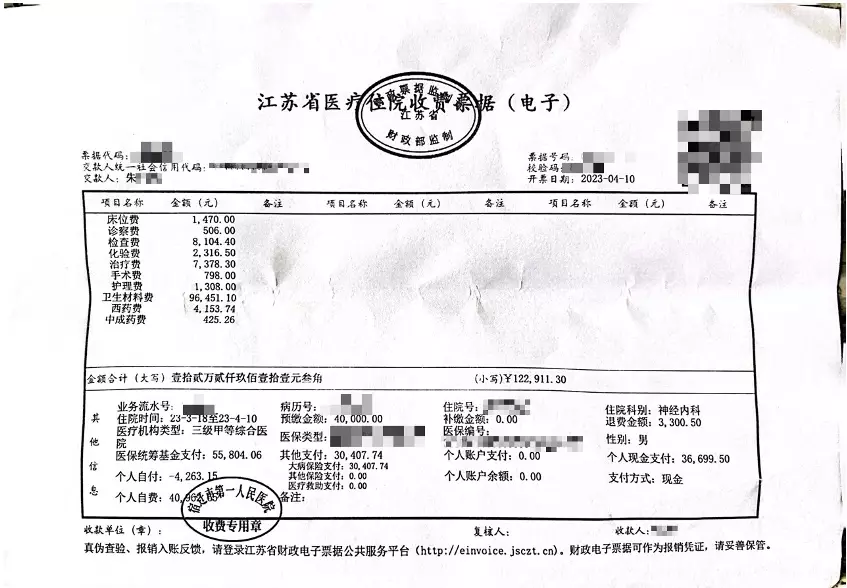

當時醫生告知家屬,如果不予血管內介入治療,患者隨時可能因動脈閉塞導致死亡。經家屬簽字同意,4月6日,齊某再次作為主刀醫生,對朱老翁進行經皮基底動脈支架植入術,術後告知家屬手術成功。手術記錄均顯示,朱老翁安裝了一枚進口Neuroform Atlas 4.5/21支架,病程記錄也多次提到「血管狹窄明顯改善」。朱老翁4月10日「康復」出院,家屬結清了住院醫療費用,合計12萬餘元,部分自費。收據顯示,其中顱內支持導管收費1.88萬,神經導絲4275元,而Neuroform Atlas進口顱內支架為4.7萬元。

朱老翁「手術成功」出院,住院費約12萬元,部分自費。